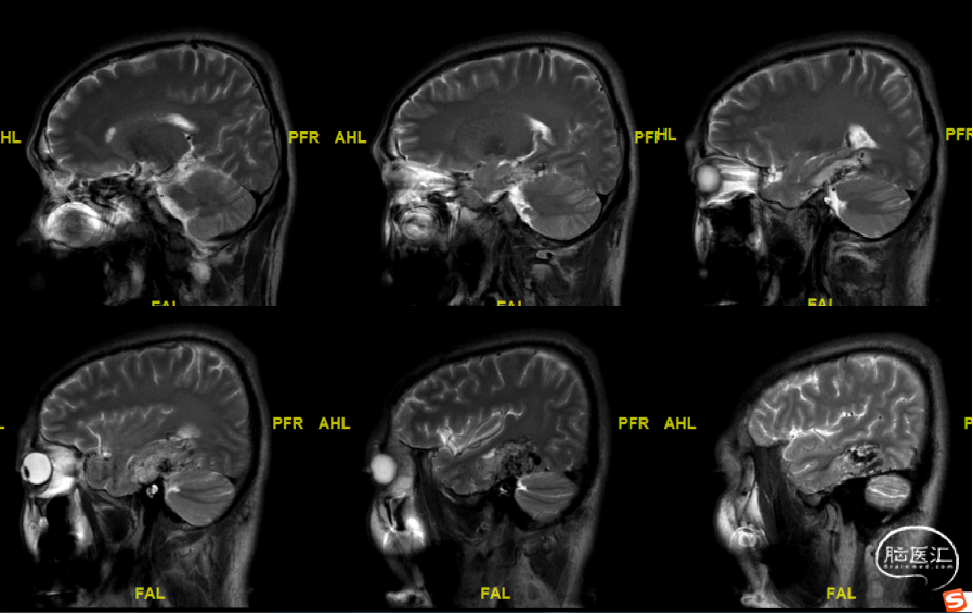

术前MRI

DTI-视辐射